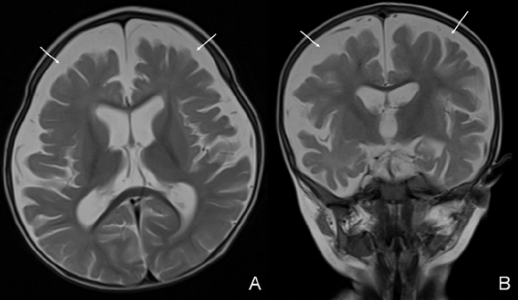

Na slikanju z magnetno resonanco sta bila vidna kortikalna atrofija in povečanje subarahnoidnega prostora. Ravni vitamina B12, hemoglobina in srednji korpuskularni volumen matere so bili 232 pg/ml, 12,2 g/dl oziroma 104,5 fL.

Ko je bil star 18 mesecev, je začel hoditi. Kontrolna magnetna resonanca lobanje, opravljena tri mesece po začetku zdravljenja, je pokazala okrevanje možganske atrofije. Širina subarahnoidnega prostora je bila v normalnem območju. Zaradi nevrološkega izboljšanja in normalnih hematoloških vrednosti je bilo zdravljenje s kobalaminom prekinjeno pri starosti 18 mesecev.

Vse kaže, da imajo dojenčki, diagnosticirani in zdravljeni pred enim letom starosti, ugodnejši nevrološki izid kot tisti, ki so bili zdravljeni pozneje. Ne smemo pozabiti, da začetno izboljšanje po zdravljenju morda ne bo dolgoročno prineslo ugodnega izida. Pri tem bolniku so opazili hitro nevrološko okrevanje; tri dni po prvi injekciji se je ponovno smejal in ni bil ne letargičen ne hipotoničen. V šestem mesecu zdravljenja je začel hoditi, ko je bil star 18 mesecev. Kontrolna magnetna resonanca lobanje, opravljena tri mesece po začetku zdravljenja, je pokazala okrevanje možganske atrofije.